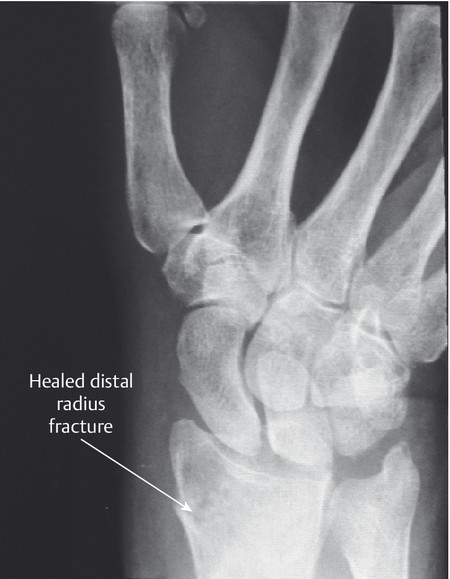

Closed rupture of extensor pollicis longus (EPL) at the wrist is the most common attrition tendon rupture. There is normally a history of distal radius fracture, often relatively undisplaced, and sometimes decades earlier. Direct repair is not possible and an extensor indicis proprius (EIP) to EPL transfer is an effective treatment.

The patient shown in Fig. 9‑1 presented to the hand trauma clinic with an inability to extend the thumb. She had been managed conservatively in cast for 8 weeks for a distal radius fracture (Fig. 9‑2). Clinical examination confirmed a ruptured EPL tendon. An EIP to EPL transfer was performed under regional anesthetic (Fig. 9‑3, Fig. 9‑4, Fig. 9‑5, Fig. 9‑6, Fig. 9‑7). The EPL which lies in the third extensor compartment is thought to undergo ischemia due to edema which consequently results in tendon necrosis and rupture.